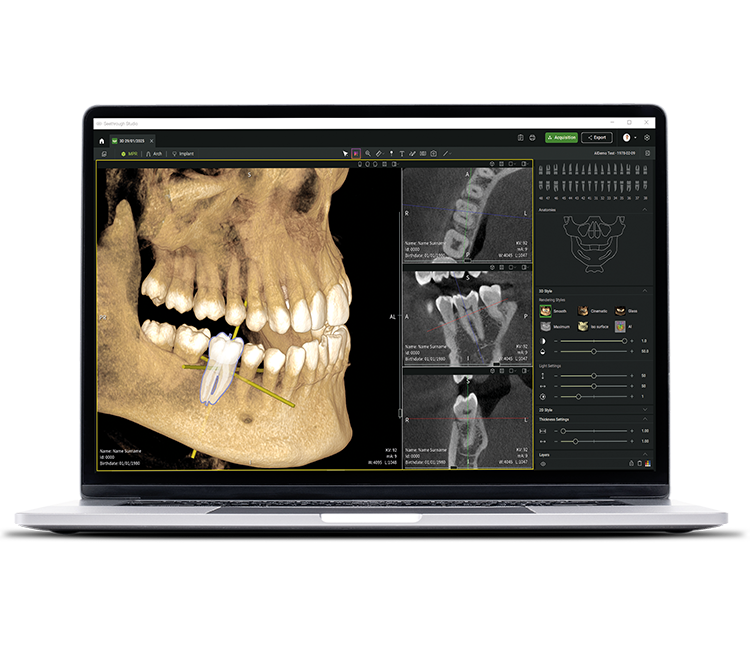

• Seethrough Studio

See tomorrow. See a new level.

In addition to sophisticated hardware technologies, the revolutionary Seethrough Studio software is a decisive factor for the high standard of the entire W&H imaging portfolio. With its beneficial features and advanced algorithms, Seethrough Studio is an all-in-one solution that takes imaging quality and digital dentistry workflows to a new level.

Seamless integration

Seethrough Studio can be easily integrated into your patient management system. You can start the software directly from the PMS without having to re-enter the patient data.

Free FOV selection on the scout image

Get the right image at the first scan: select the required FOV in the scout preview and freely adjust the region of interest. This ensures accurate positioning of the FOV and avoids the need to re-expose the patient.

Patient motion and position correction

The advanced patient motion correction algorithm elevates image quality to new levels in both 3D and 2D imaging. 2D images are further enhanced by a 21-layer autofocus system, seamlessly integrated with a patient positioning correction.

Metal artefact removal (MAR)

Restores image integrity by eliminating interference from metallic artefacts, and allows you to review images with MAR on or off – for a highly flexible visualisation and improved diagnostic accuracy.

Implant planning tool integrated

In addition to the outstanding image quality and intuitive operation, Seethrough Studio offers numerous useful features such as the standard integrated implant planning tool for easy visualisation and preparation of the treatment.

AI-supported functions

Seethrough Studio utilises various AI tools for imaging enhancement, including 3D volume alignment, tooth segmentation, arch line generation, automatic nerve tracing as well as useful support for pathology detection.